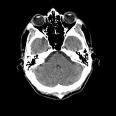

Las tecnologías de imagen, como la tomografia axial computerizada (TAC) o la resonancia magnética, se pueden asociar con ingresos hospitalarios más cortos. Esta reducción del periodo de hospitalización se traduce, a la postre, en un ahorro de dinero. Así lo sostienen los autores de un nuevo trabajo aparecido en 'Journal of The American College of Radiology'.

Los expertos sostienen que las pruebas de imagen pueden disminuir los gastos gracias a su influencia, entre otras, en la reducción de los tiempos de estancia en el hospital. Para probar su hipótesis, estudiaron 10.000 casos de ingresos en los que se recurrió, por lo menos en una ocasión, a este tipo de tecnología médica. Más en concreto, se optó por el TAC, la resonancia o a la escintigrafía (una prueba de Medicina Nuclear).

Además del tipo de examen médico, los especialistas del centro de Boston analizaron si éste se realizó antes o después del ingreso hospitalario. Intentaron "demostrar que los pacientes que se someten a una prueba de imagen al principio de la admisión cuentan con periodos más cortos de hospitalización y determinar los tipos de análisis [...] y los principales diagnósticos para los que esto sería más importante".